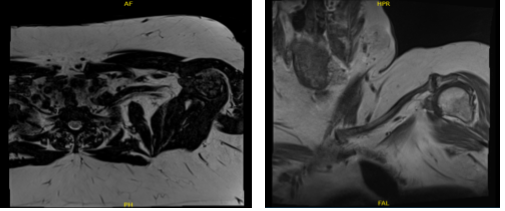

MRI second result